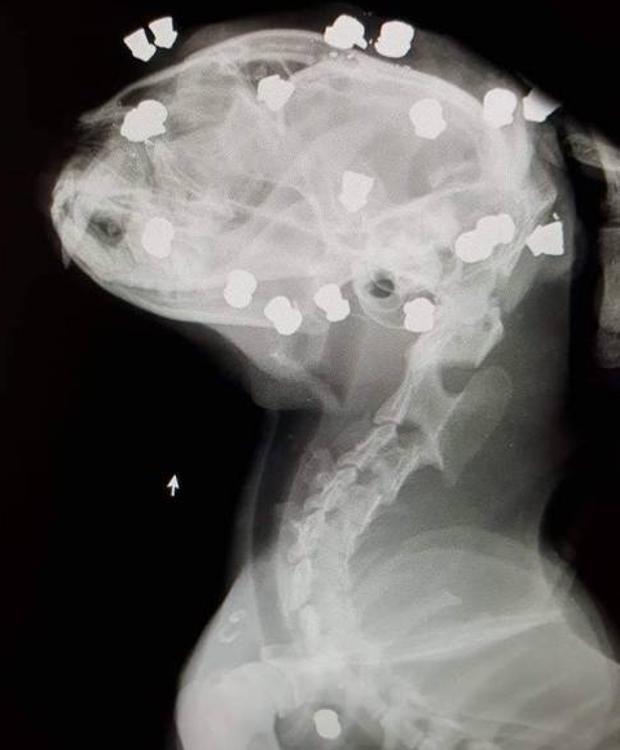

Sacrificio cero, una ONG protectora de la vida animal, ha denunciado el hallazgo en el municipio de Lardero (La Rioja) de un gato con 18 perdigones incrustados en su cabeza.

El animal había sido disparado con una carabina hasta en 18 ocasiones , si embargo, el felino sobrevivió y se encuentra estable, aunque puede sufrir la pérdida de un ojo, tal y como ha informado 'larioja.com'.